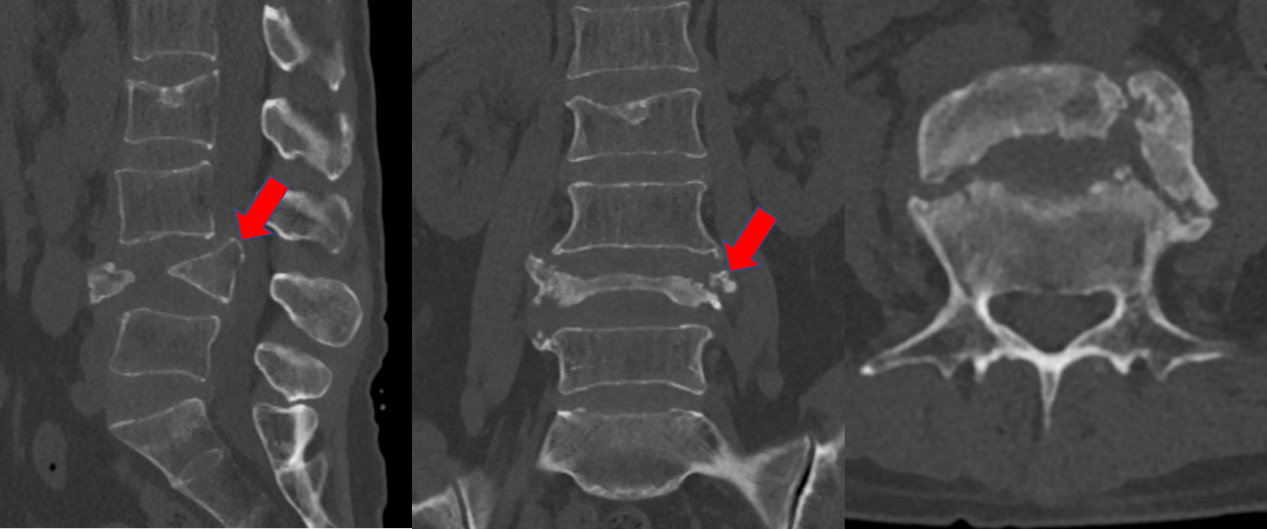

L4椎体陈旧性骨折,椎体高度塌陷严重

患者L4椎体几乎完全压缩,骨块已突入椎管,椎管严重狭窄

L4水平椎管狭窄明显,造成患者双下肢乏力、麻木